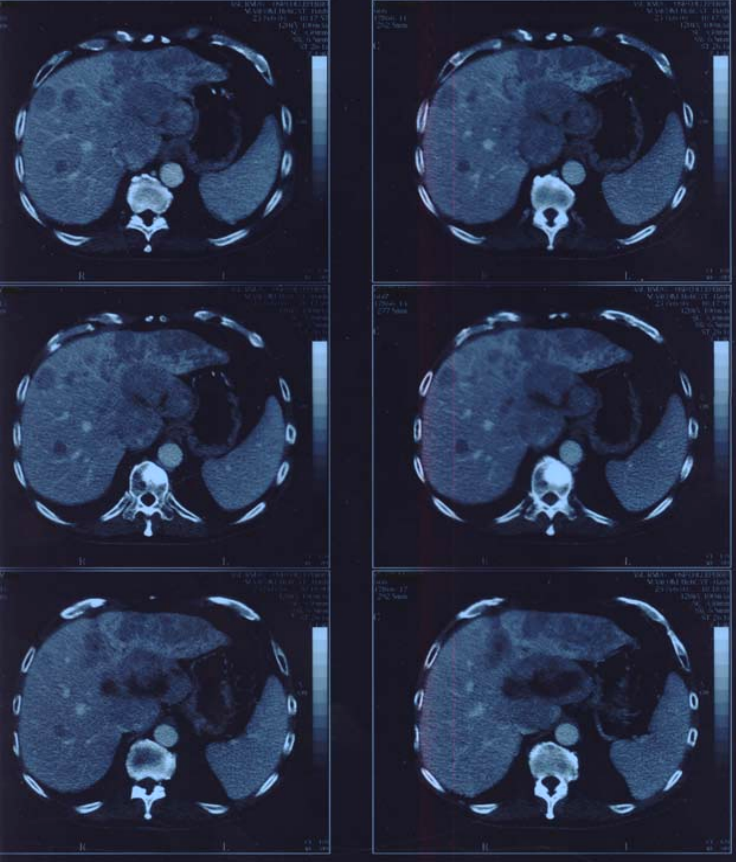

Figure2